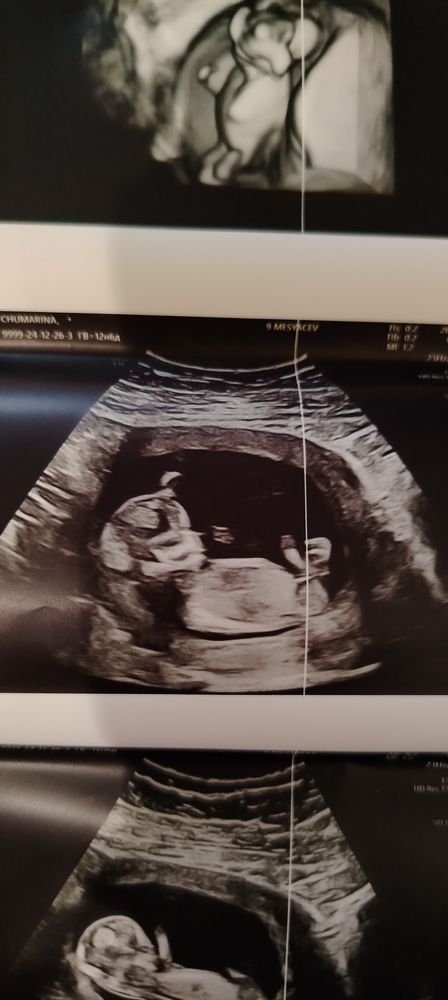

Пол ребенка

На первом фото половой бугорок не ровно горизонтальный, что говорит о том, что это может быть и мальчик, еще и расположение его мочевого пузыря. А на втором малыш повернулся чуть и кажется буговорок уже ровно горизонтальным. У меня также было, только одно фото было как у вас 1-ое. Узист говорил 50/50 и в итоге жду мальчика💙 Срок еще маленький у вас чтобы 100% говорить пол ребенка, да и половой бугорок еще может измениться. Так что сделайте узи на сроке 17-20 недель

Не, тут прям девчонка) половой бугорок параллельно спинке)

Это девчоночка))) а подскажите на каком сроке узи делали? Так видно хорошо)))

Ксения, 12 недель 5 дней

Какой пол? Помогите узнать пол